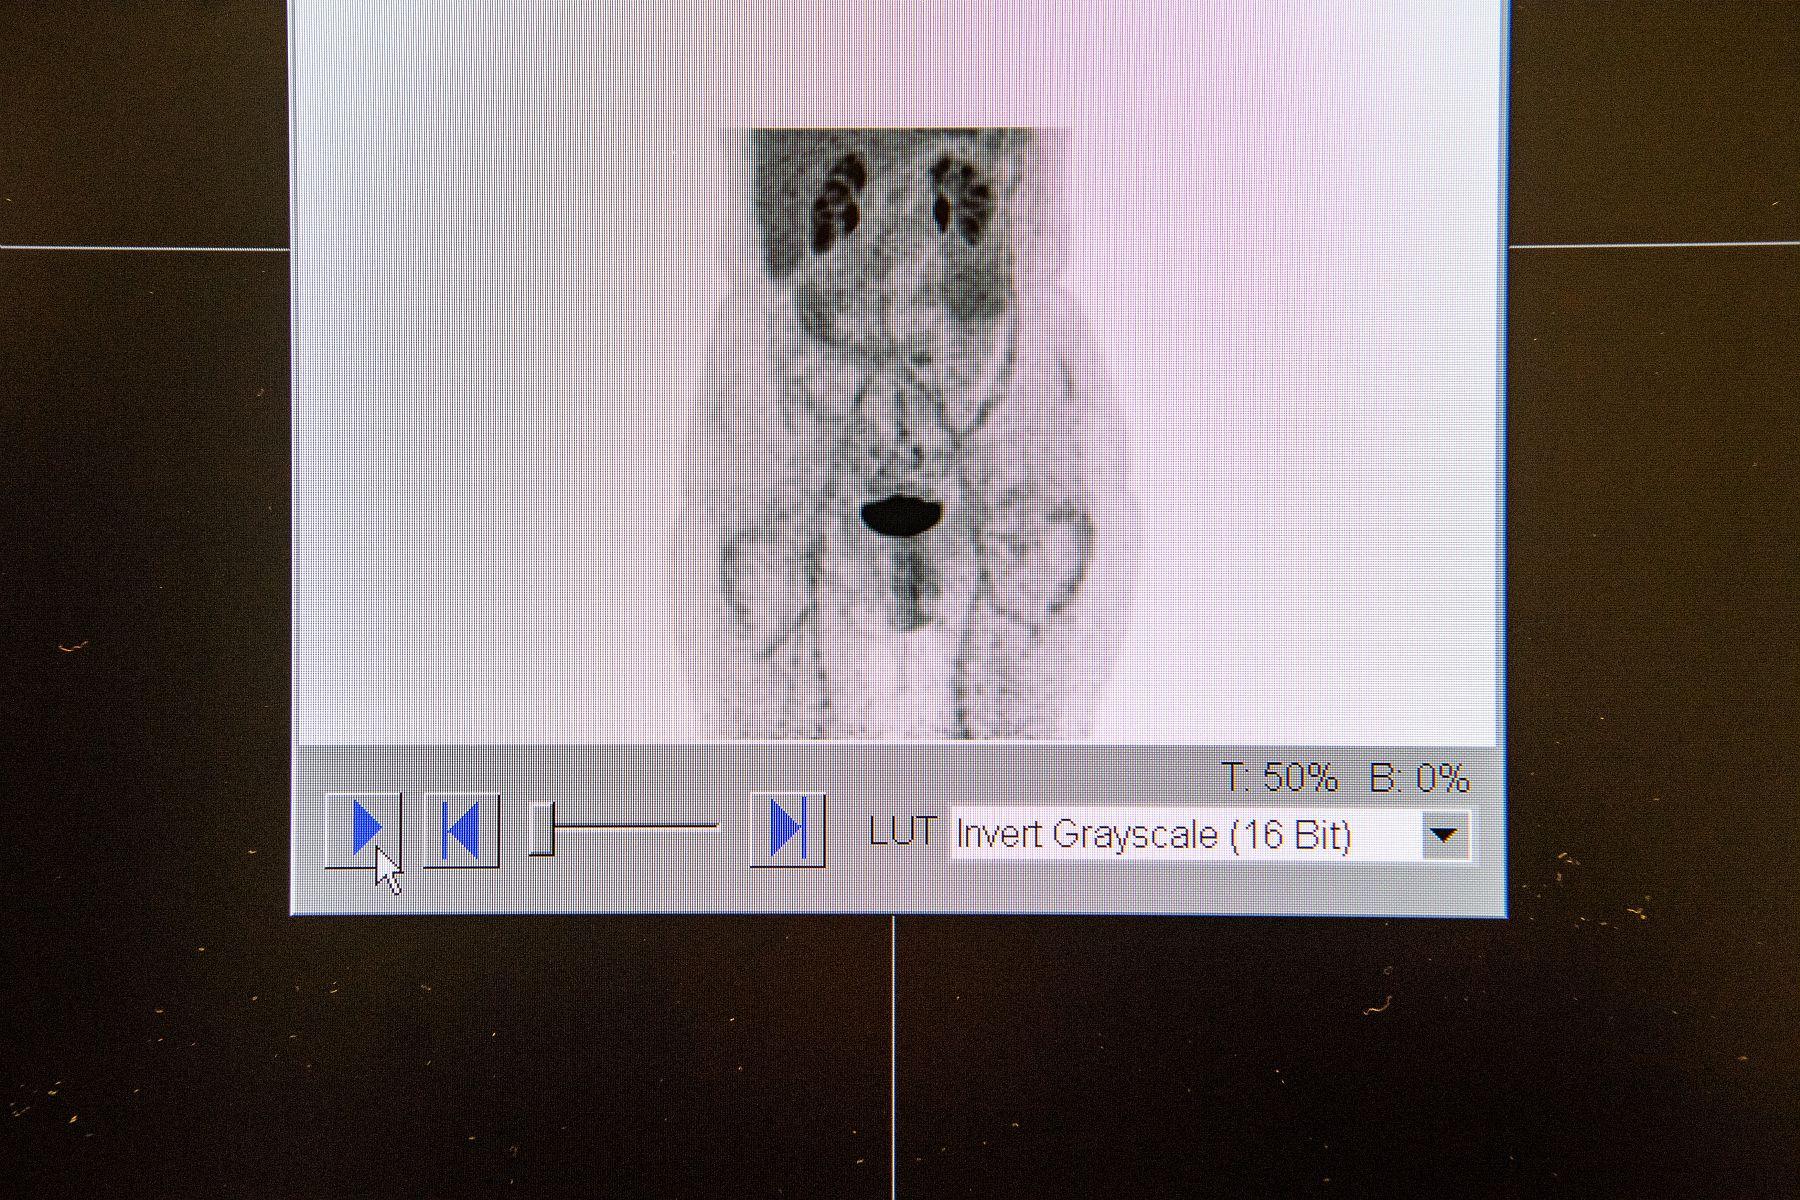

Image d'une tomographie "basse dose" en cours de reconstruction par l'appareil TEP-TDM (tomographie par émission de positon couplée à un tomodensitomètre à RX). La nouvelle caméra a permis de réduire l’exposition des patients tout en conservant une bonne qualité d’image.